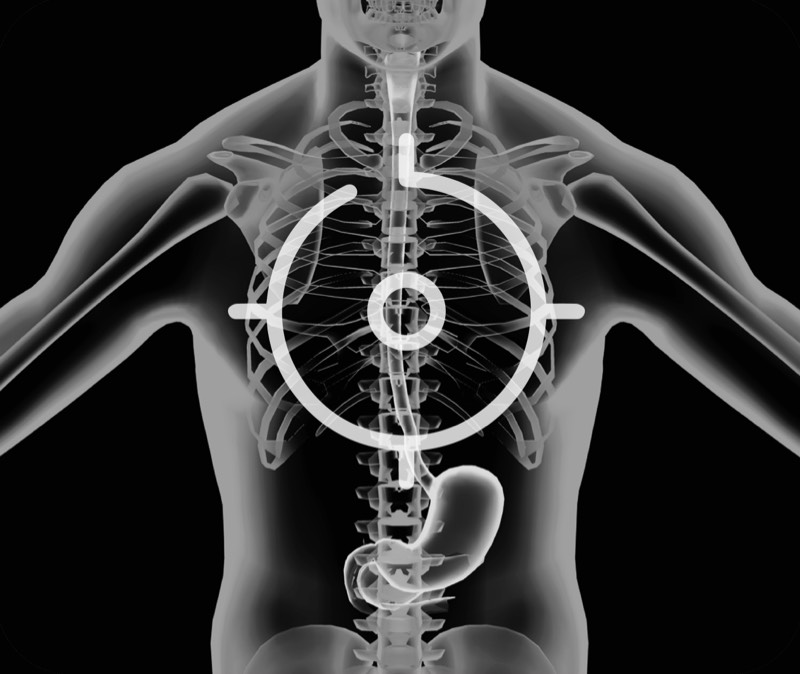

肝左叶和肝静脉的横截面